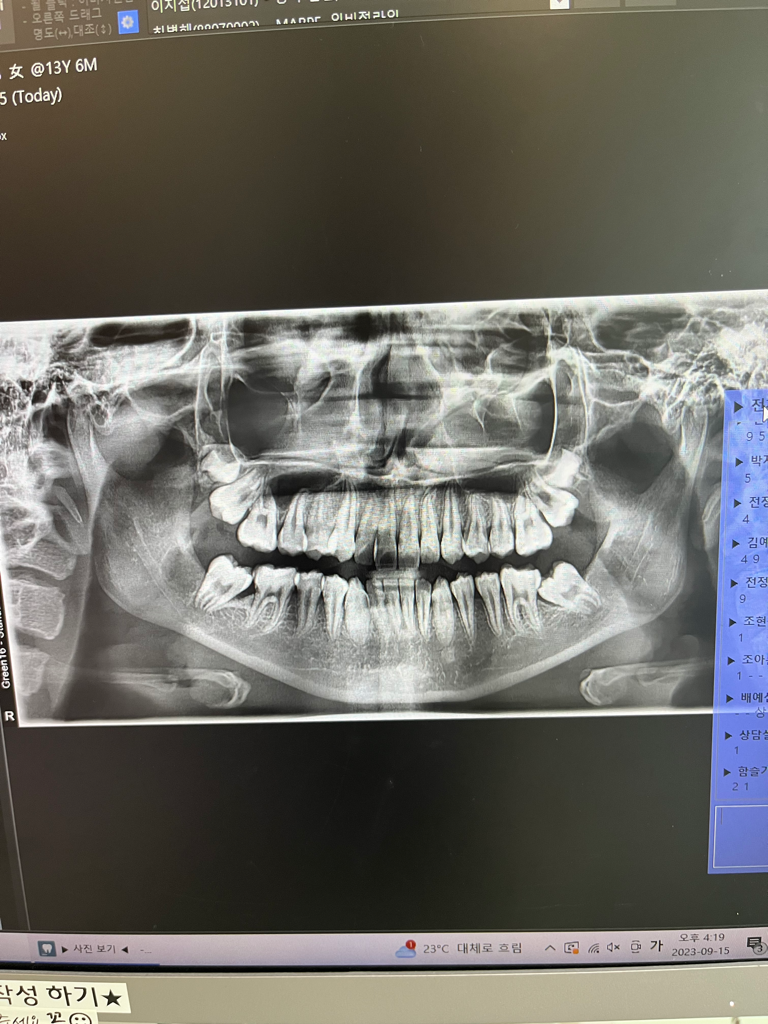

중1딸아이 치아엑스레이에요..꼭 전체교정 필요할까요??

전 어금니누운거 부분교정만 하고 싶은데

• 2번 째 사진